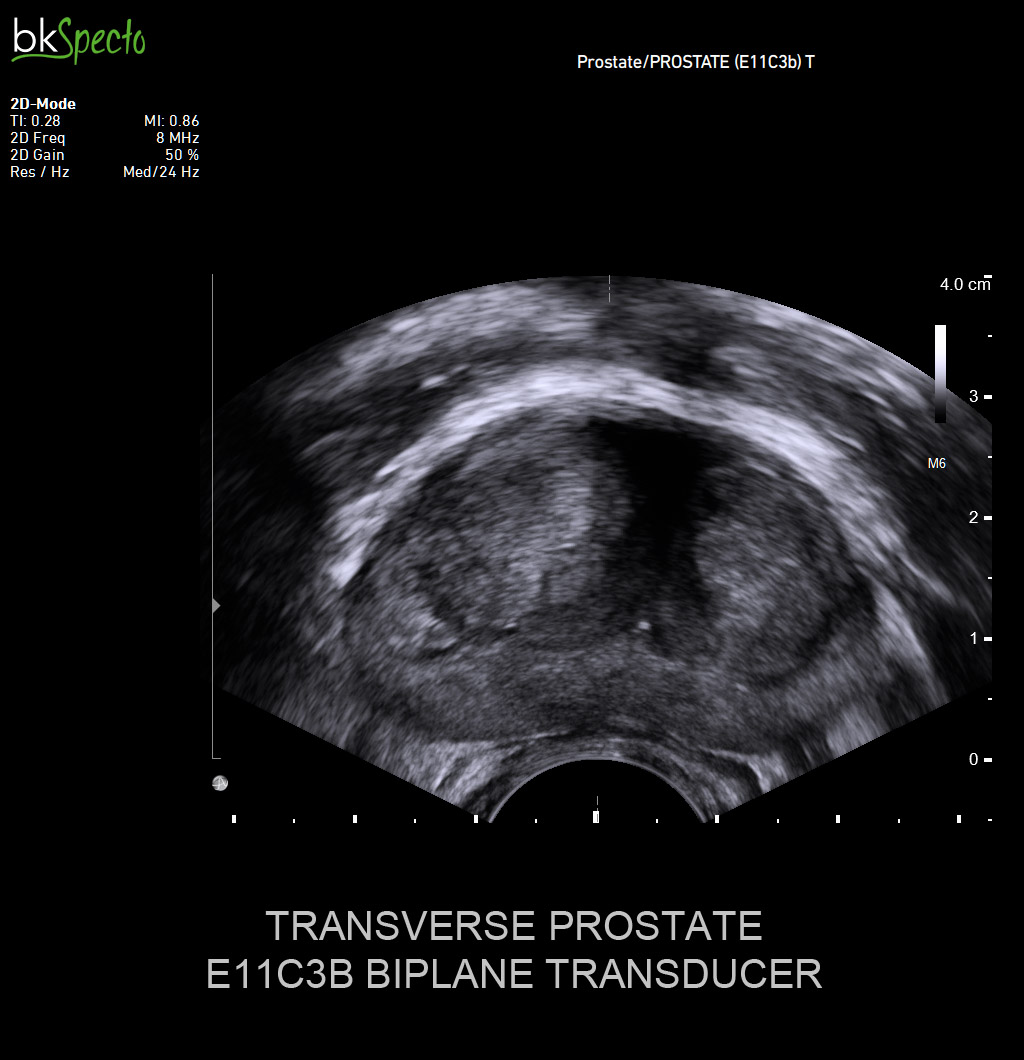

- Modul sinh thiết và điều trị u xơ tiền liệt tuyến (TUR) qua ngả trực tràng dưới dướng dẫn siêu âm _Prostate Imaging & Biopsy: Đặc biệt kỹ thuật điều trị u xơ tiền liệt tuyến bằng hạt phóng xạ (brachytherapy)